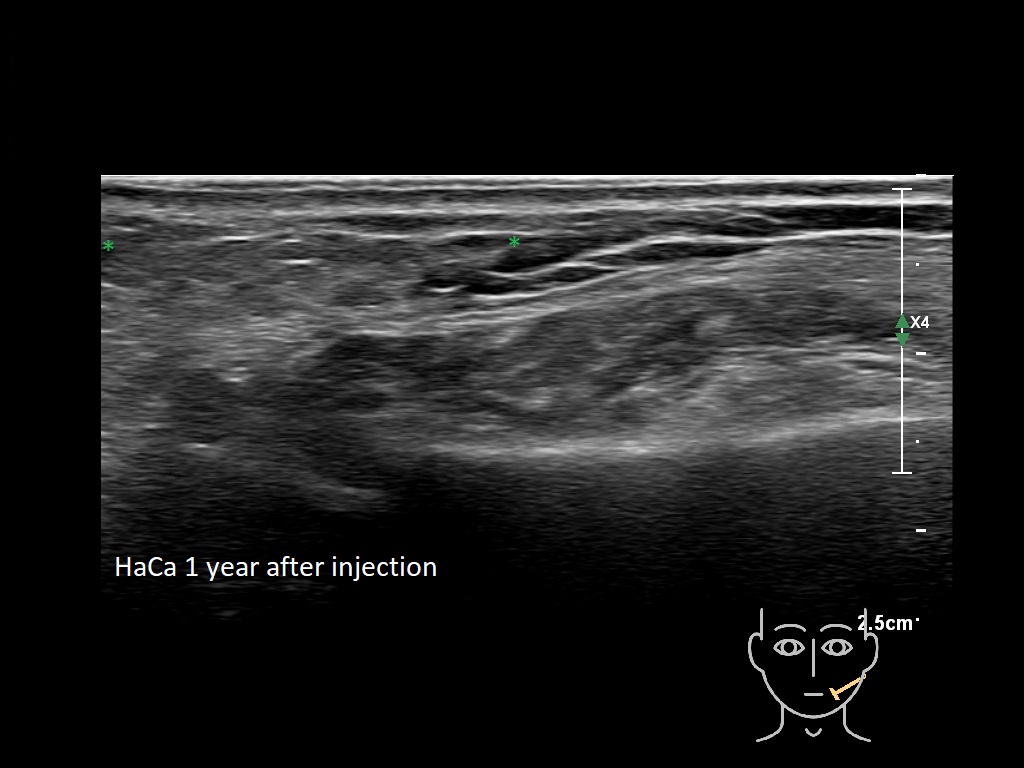

Fillers

Fillers

Draw in the second image below where the fillers are located. To check if your answer is correct, swipe the first image to the right.

HAca 2a

-